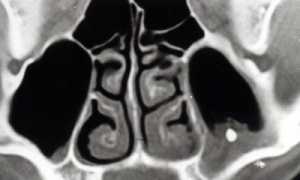

Диагностика

Для постановки верного диагноза необходимо сдать общий анализ крови, кровь на иммуноглобулин Е. Повышение эозинофилов в анализе крови — признак аллергического процесса либо глистной инвазии, которая также может давать аллергические реакции. Врач тщательно опрашивает родителей: о питании грудного ребенка помимо вскармливания грудью, жилищных условиях, симптомах.

Врач-аллерголог, при подозрении на аллергическую природу ринита, назначает кожные аллерготесты, выявляющие реакцию гиперчувствительности на наиболее распространенные аллергены.